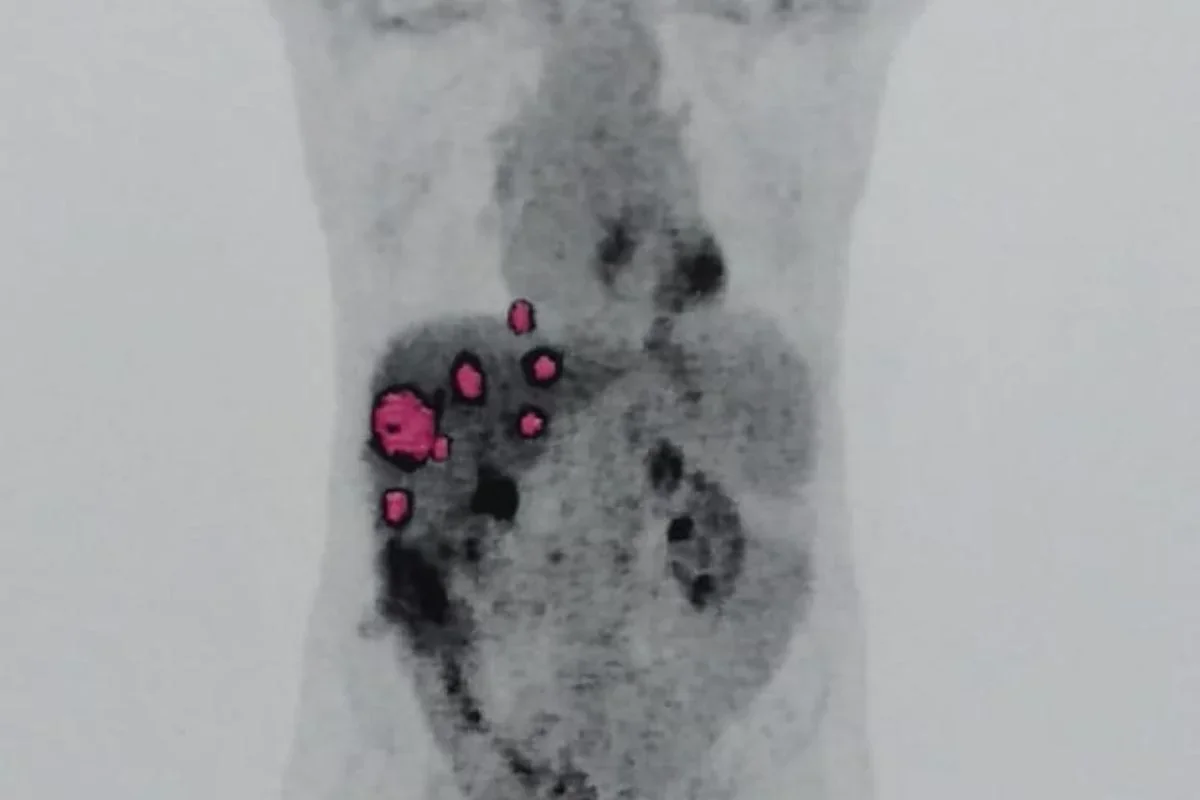

A análise foi realizada no Hospital Albert Einstein, mesmo local onde o transplante foi feito e onde o paciente atualmente realiza quimioterapia. Em agosto do ano passado, médicos identificaram metástases nos pulmões de Geraldo. O laudo apontou que o tumor foi transmitido com o órgão, possivelmente por células isoladas ou micrometástases que só se manifestaram posteriormente.